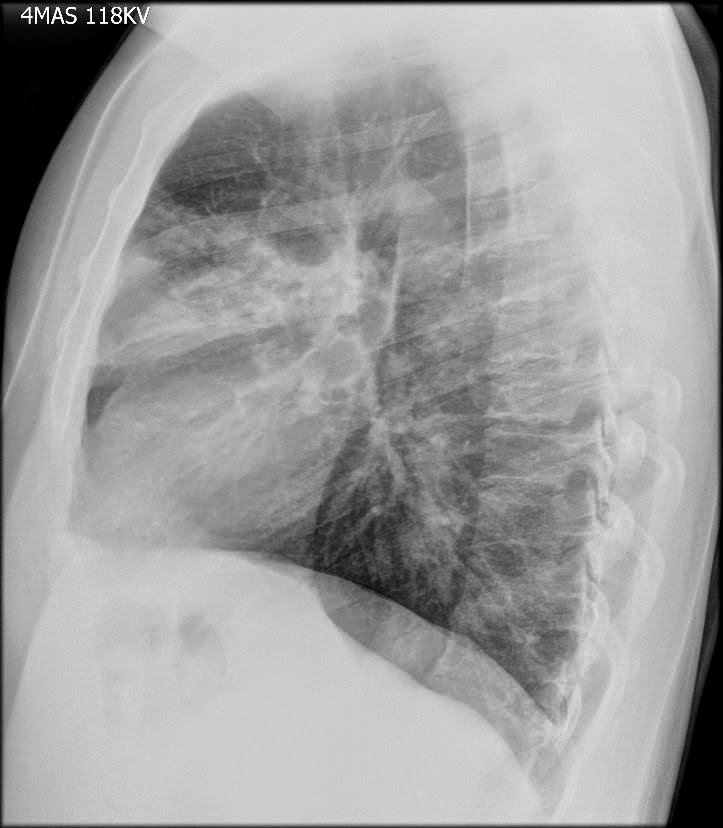

Caso Interesante #4

Adulto masculino, 1 semana de fiebre y malestar general.

¿Dónde esta ubicado el hallazgo?